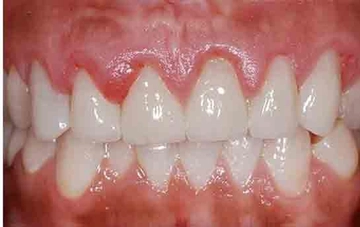

Kök Kalmasının SonuçlarıDiş çekiminden sonra kök kalması, bazı olumsuz sonuçlara yol açabilir: